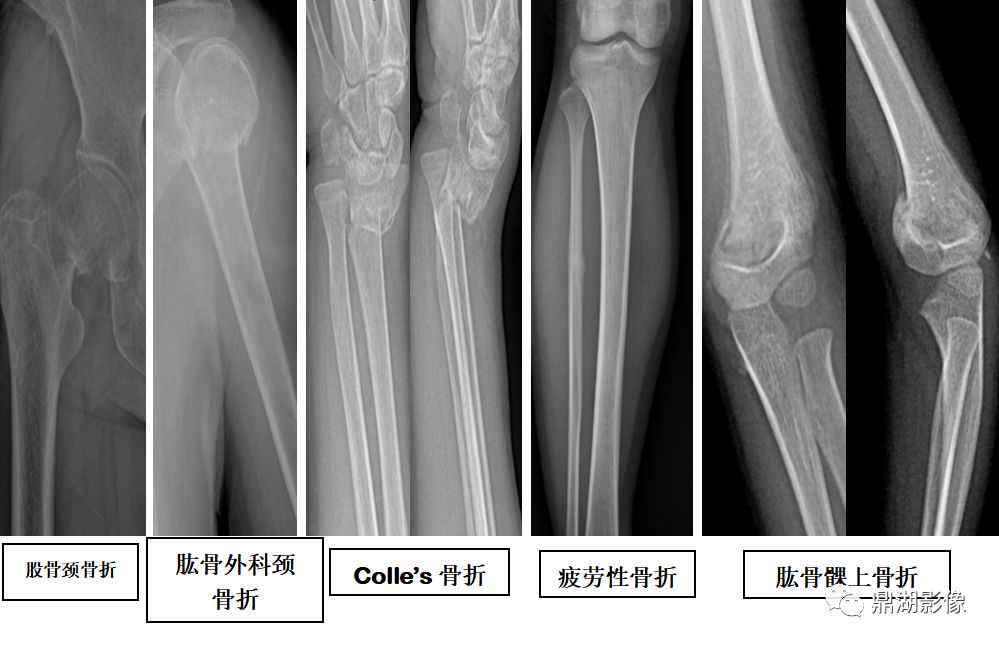

四肢骨折

骨折类型